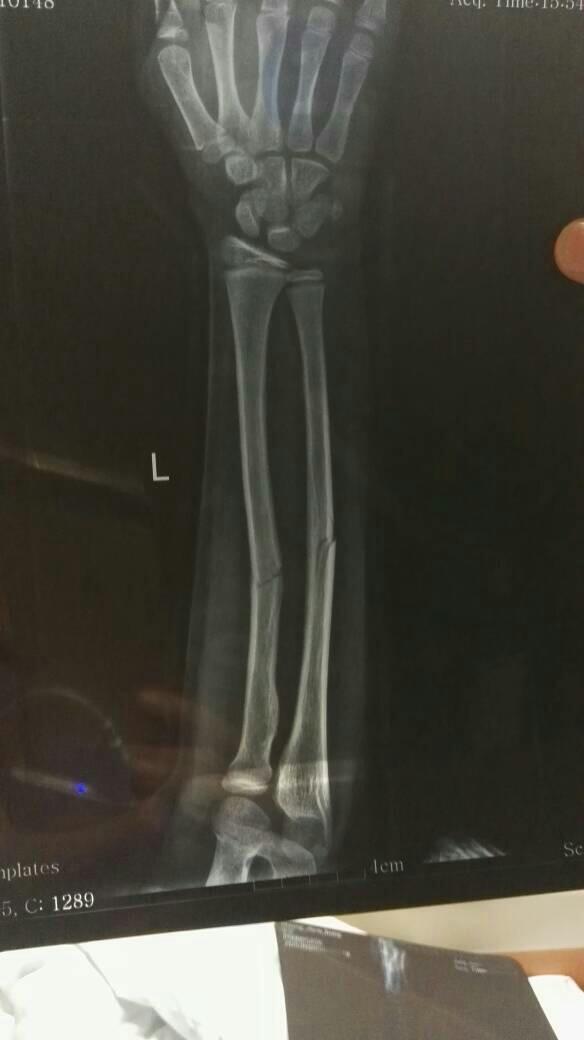

小儿左胳膊尺骨骨折复位后的标准 小儿左胳膊尺骨骨折复位后的标准这样需要再复位吗 点击展开 匿名用户 2016-08-02 13:39 满意回答 个人感觉卫录是可以的,固定好,不继续位置变它吊动,应该怪佳躬没有太大问题! _ 2018-01-01 07:29 宝宝知道提示您:回答为网友贡献,仅供参考。 相关问题 尺骨骨折后手法复位15天手掌还是很肿怎么办? 宝宝俩岁胳膊具鹰嘴尺骨骨折医生说好了胳膊就伸不直了,是真的吗 我家孩子七岁胳膊尺骨骨折绑板两天说胳膊痒是怎么回事